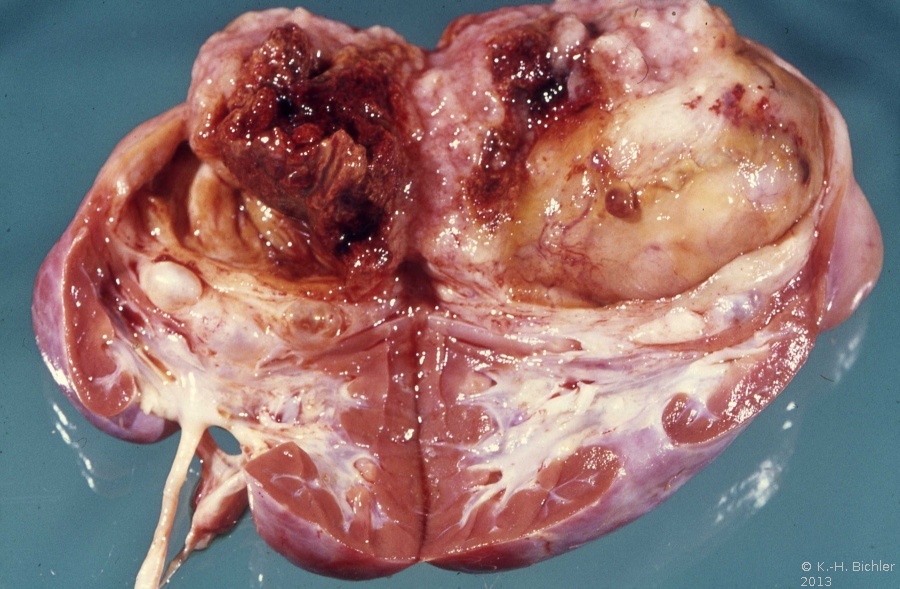

Die Beziehungen zwischen dem Wilmstumor und anderen nephroblastomatösen Tumoren wie dem zystisch partiell differenzierten Nephroblastom, dem zystischen Nephrom, der Nephroblastomatosis und dem multilokulären, zystischen Nierenzellkarzinom sind nicht eindeutig und bleiben kontrovers (Abbildung 3).

Im Zusammenhang mit der Heterogenität bzw. der molekularen Genetik der Wilmstumoren ist das Vorkommen einer prämalignen Struktur (Präkanzerose), der "Nephroblastomatosis" zu nennen. Es handelt sich um multizentrische, bzw. diffuse Nester von unreifem, nephrogenem Gewebe in Bezirken von normalen Nierenanteilen. Die Nephroblastomatosis kann in ein malignes Nephroblastom übergehen (s. Abbildung 3).